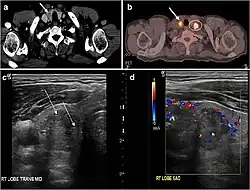

Fig. 3. An incidental PTC in a 62-year-old male patient with lymphoma. a, b Enhanced axial CT scan and fused PET/CT scan of the neck demonstrate a well-defined, hypodense right thyroid nodule (white arrow) with high FDG uptake. The FDG-avid uptake in the left side (circle) is related to patient's known lymphoma, which resolved after treatment. c, d Transverse greyscale and sagittal colour Doppler ultrasound of the neck demonstrate a right thyroid irregular hypoechoic lesion with some micro-calcifications (white arrows) and increased vascularity.[1]